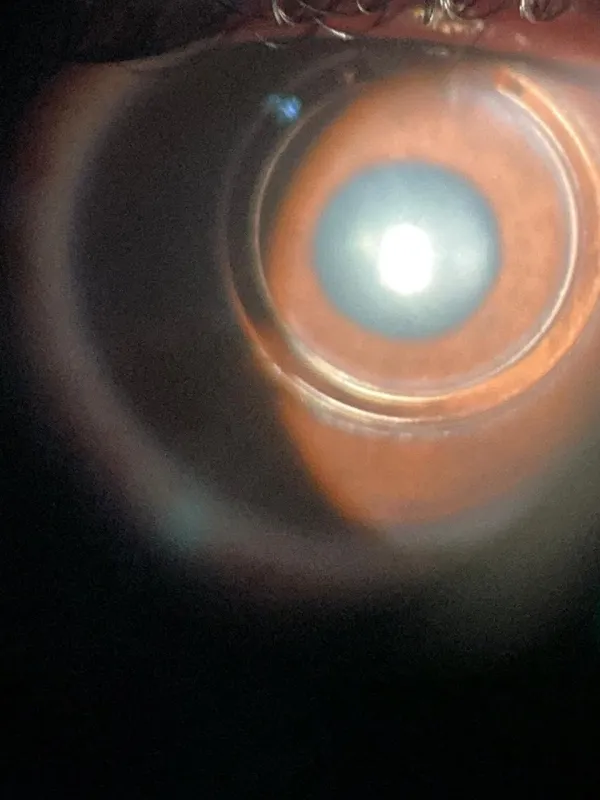

O ceratocone é uma doença de etiologia multifatorial, com componente genético envolvido e em muitos casos pode originar-se ou agravar-se pelo hábito de coçar os olhos. Os danos causados por coçar os olhos podem ser elevados: o desenvolvimento de uma doença que pode levar à perda progressiva da visão. O ceratocone pode ser leve, moderado ou severo e em alguns casos o paciente com ceratocone pode beneficiar-se do implante do anel de ferrara valor.

Nos casos moderados e severos, geralmente a prescrição de óculos geralmente não é suficiente para a obtenção de uma boa visão devido ao grau elevado de irregularidade corneana e astigmatismo. Nesses casos o anel de ferrara valor é uma excelente opcão pois permite uma maior regularização da superfície corneana, reduzindo o astigmatismo, melhorando a visão, facilitando a adaptação de lentes de contato rígidas e permitindo que em muitos casos a prescrição de óculos tenha efeito.

O anel de ferrara valor consiste em um segmento de um material chamado PMMA (polimetil-metacrilato) que é implantado de forma artesanal dentro da córnea de pacientes com ceratocone.

A técnica de implante do anel de ferrara valor dentro da córnea pode ser manual ou com o uso do laser de Femtosegundo. Na técnica manual é utilizado um tunelizador que cria um túnel dentro da córnea que vai ser o local onde será implantado o Anel de Ferrara. No caso do laser de Femtosegundo, o túnel é criado com o uso do aparelho que cria um túnel a laser na espessura e profundidade corretas permitindo a implantação do anel de ferrara valor.

A implantação do anel de ferrara valor utilizando o laser de Femtosegundo tem um preço mais elevado e oferece mais segurança e menos complicacões a curto e longo prazo quando comparada à implantação do anel de ferrara valor com a técnica manual. A clínica AORP realiza a maioria das cirurgias de anel de ferrara valor com uso de Laser de Femtosegundo.